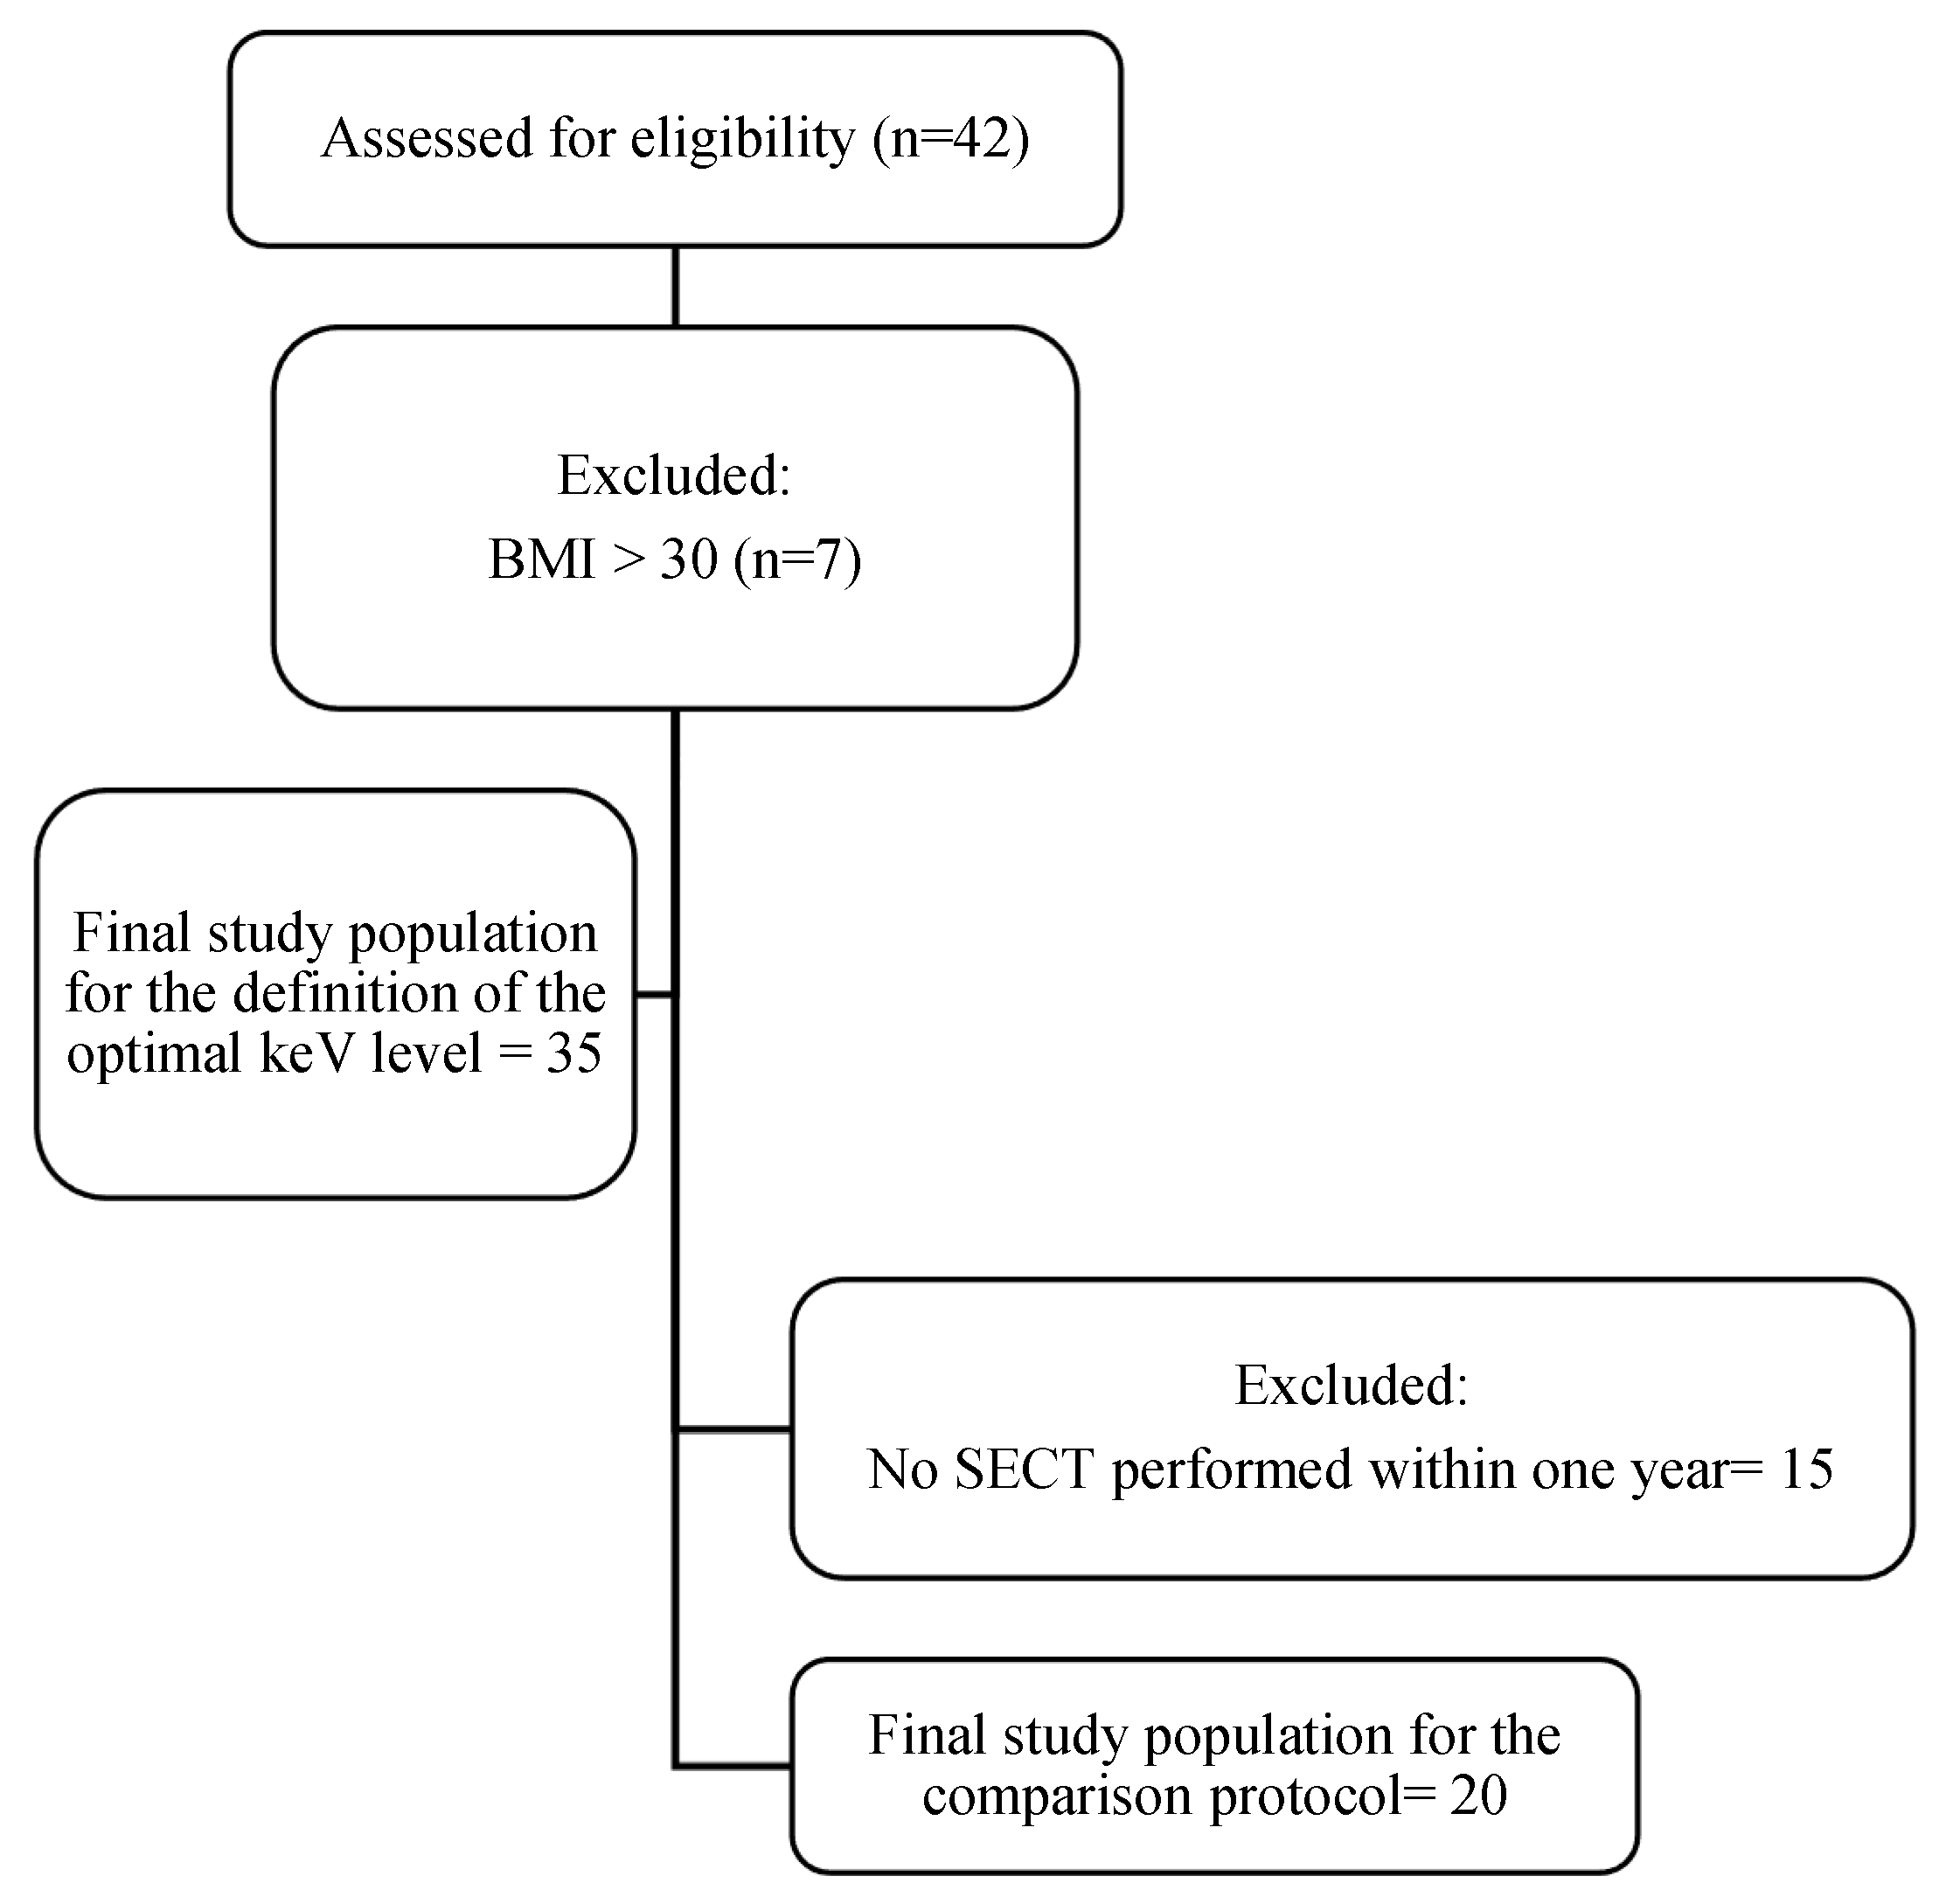

3.1. Patient Population